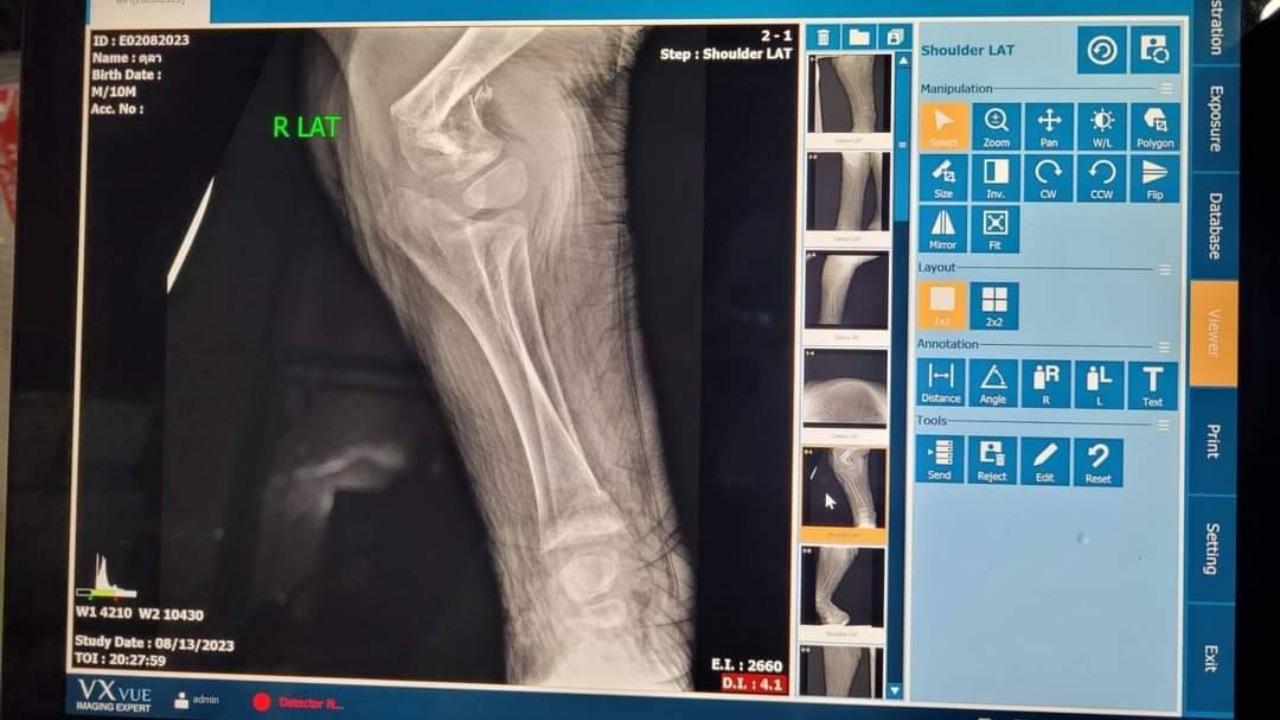

ต่อมาเวลา 18.00 น. ลูกช้างป่า (ตุลา) เริ่มมีอาการหายใจช้าลง ลิ้นเริ่มมีสีซีด มีภาวะหัวใจหยุดเต้น สัตวแพทย์และเจ้าหน้าที่จึงได้เข้าช่วยเหลือปฐมพยาบาลเร่งด่วน โดยการทำ CPR เพื่อกระตุ้นการหายใจ ลูกช้างป่าไม่มีการตอบสนองต่อการช่วยชีวิต และเสียชีวิตในเวลาต่อมา สำหรับสาเหตุการเสียชีวิตเบื้องต้น เกิดการภาวะบาดเจ็บรุนแรงของกระดูกต้นขาหน้าทั้ง 2 ขาหัก (Humerus fracture) ทำให้เกิดสภาวะช็อกจากการบาดเจ็บรุนแรงตามมา (Pain shock)

ขณะที่ นายเผด็จ ลายทอง ผู้อำนวยการสำนักอนุรักษ์สัตว์ป่า ร่วมกับทีมสัตวแพทย์ ทำการชันสูตรเพื่อหาสาเหตุและเก็บตัวอย่างส่งตรวจทางปฏิบัติการ เพื่อยืนยันถึงสาเหตุการเสียชีวิต ปรากฏว่า สาเหตุหลักในการเสียชีวิต เกิดจากสภาวะกระดูกบางทั่วร่างกาย โดยเฉพาะบริเวณขาหน้า (ด้านบน) ทั้งสองข้าง พบการสลายของกระดูก ทำให้กระดูกแตกหักละเอียด ผิดรูป ซึ่งเป็นสาเหตุของอาการไม่ล้มตัวลงนอน และเล่นกับพี่เลี้ยงตามปกติ อวัยวะภายในร่างกายพบว่า ลำไส้มีความแดงผิดปกติ และสัตวแพทย์ได้ทำการเก็บตัวอย่างอวัยวะทั้งหมด รวมถึงกระดูก ส่งทางห้องปฏิบัติการ คณะสัตวแพทยศาสตร์ มหาวิทยาลัยเกษตรศาสตร์ วิทยาเขตกำแพงแสน คณะสัตวแพทยศาสตร์ จุฬาลงกรณ์มหาวิทยาลัย คณะสัตวแพทยศาสตร์ มหาวิทยาลัยมหิดล และศูนย์พัฒนาการทางสัตวแพทย์ภาคตะวันออก กรมปศุสัตว์